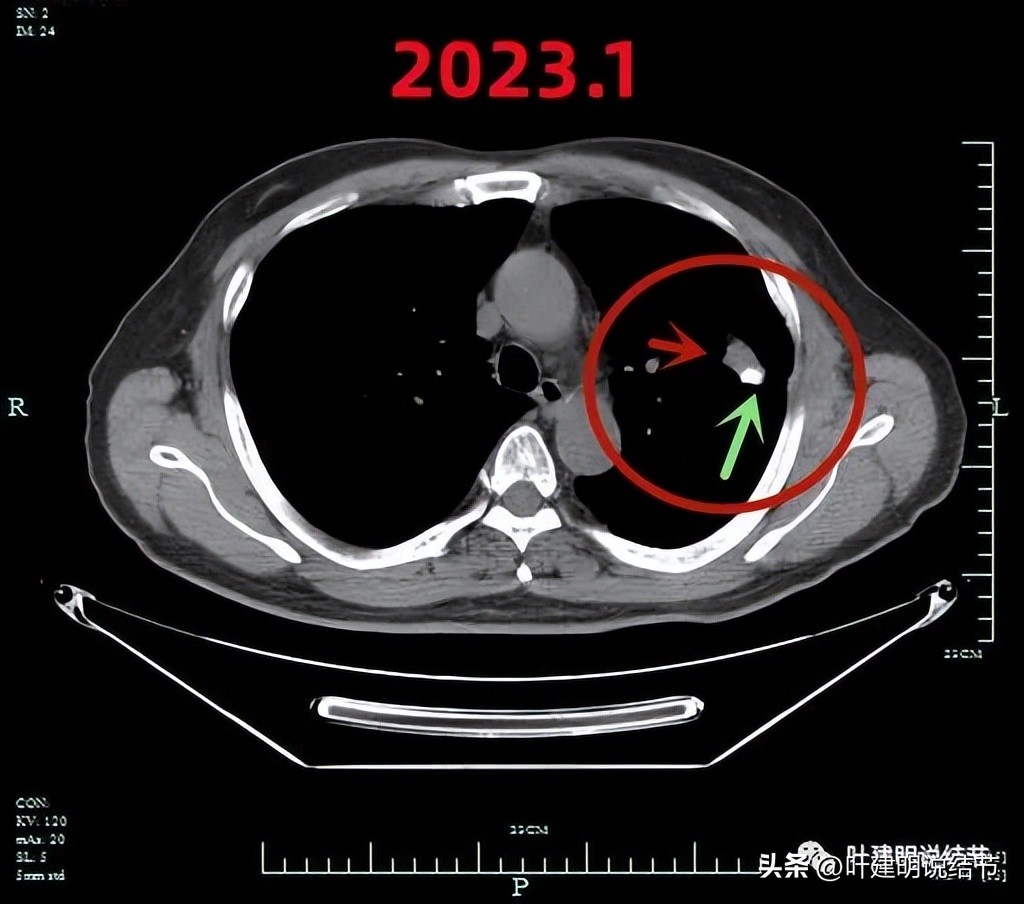

平扫纵隔窗见病灶伴有钙化(绿色箭头)

增强CT见病灶处的样子。

有钙化是不是考虑良性的呢?一般来说病灶伴钙化容易是良性,但这个病例恶性的影像太多太明显,所以再来看PET影像:

肺穿刺:红色箭头示病灶;绿色示穿刺针。

穿刺致气胸。